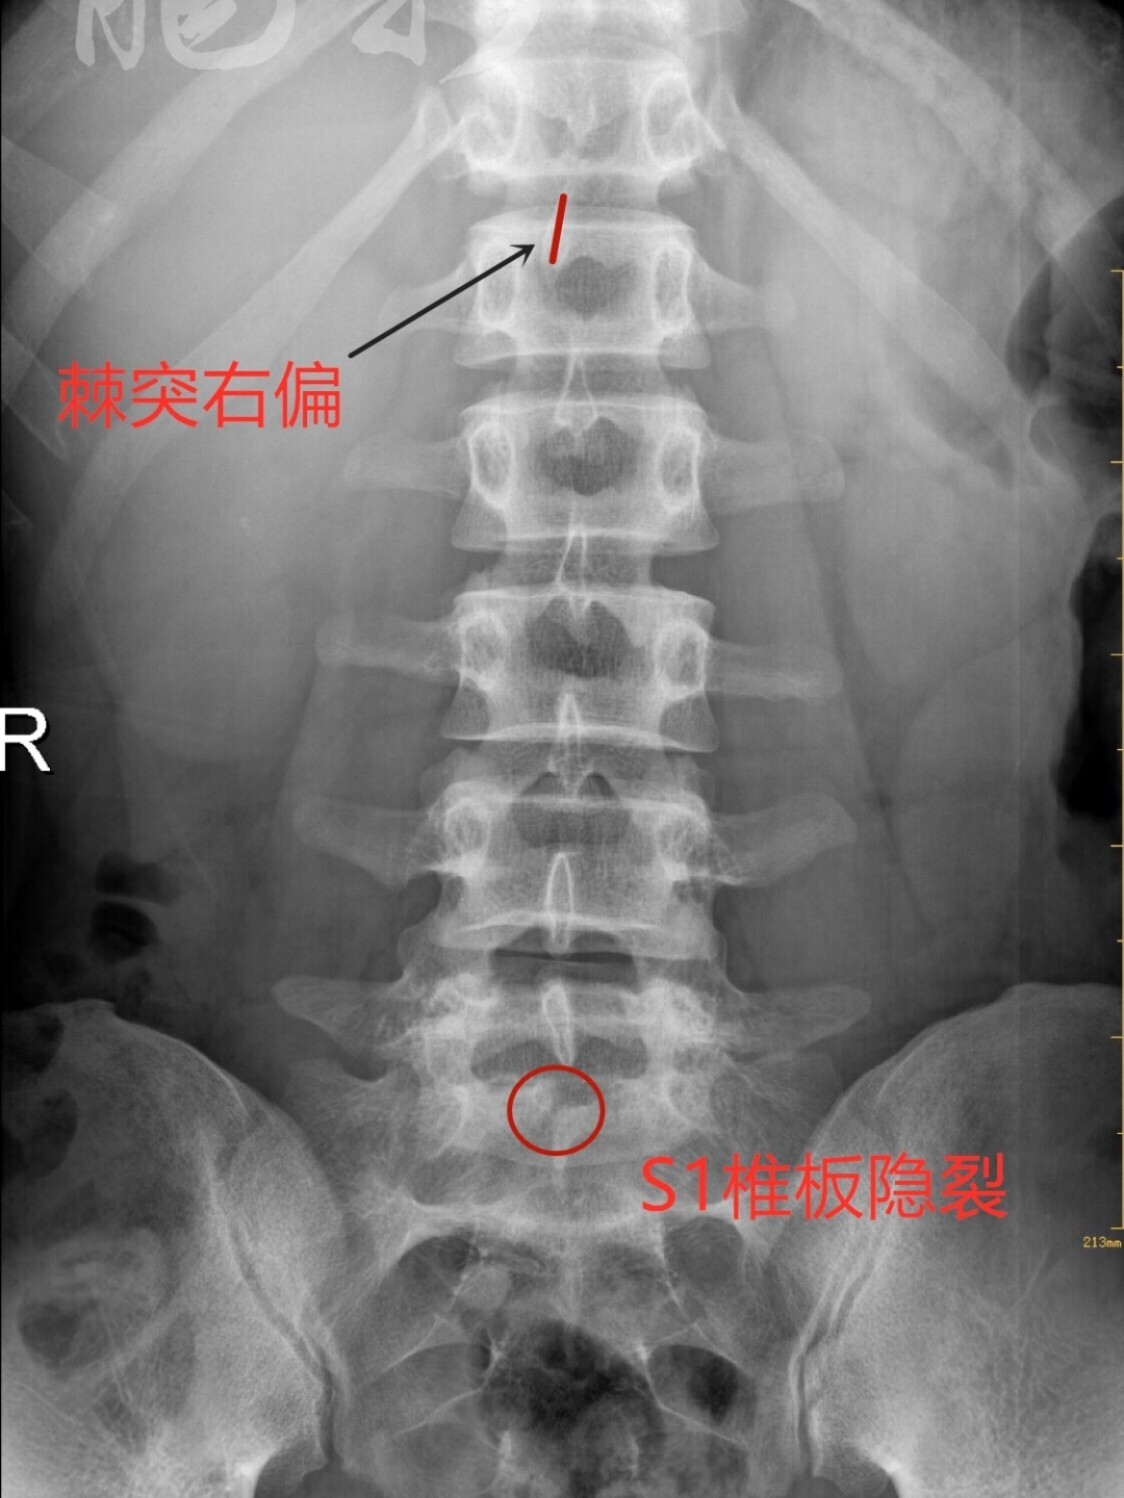

隐性脊柱裂能治愈吗?

1、不可自愈的情况若隐性脊柱裂伴有尾端发育不良泌尿系统畸形胃肠道畸形等症状,此时隐性脊柱裂不能自愈需要通过外科手术治疗相应的伴随症状,隐性脊柱裂才能得到治愈。 2、儿童隐性脊柱裂一般不会自愈,但多数情况下可随生长发育...